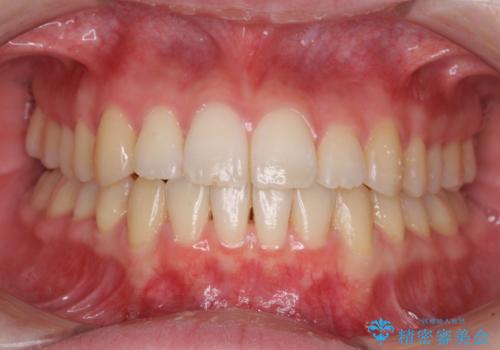

みるみる歯並びが整っていったため、「しっかりと毎日22時間以上装着できるのだろうか」という患者様自身が抱いていた不安も払拭されました。

口元を見られているという視線を気にすることなく笑えるようになり、患者様には大変満足していただきました。